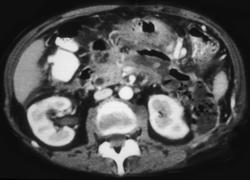

问题 女性,34岁,寒战、高热、急性中上腹偏左腹痛,压痛,CT扫描如图,最可能的诊断是 ( )

选项 A、胰腺癌 B、胰腺转移癌 C、胰腺脓肿 D、慢性胰腺炎急性发作 E、急性胰腺炎

答案 C